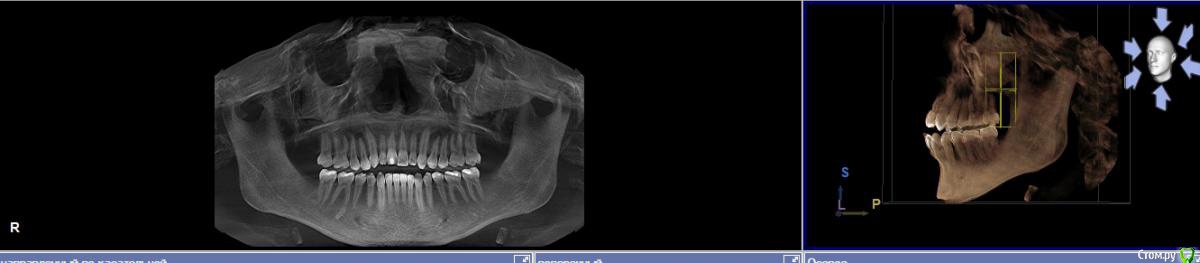

Открытый прикус, вертикальный рост челюсти. 19 летний возраст.

В добавок язык пихающий верхние зубы. (не смыкаются 4 передние)

Снимок прилагаю.